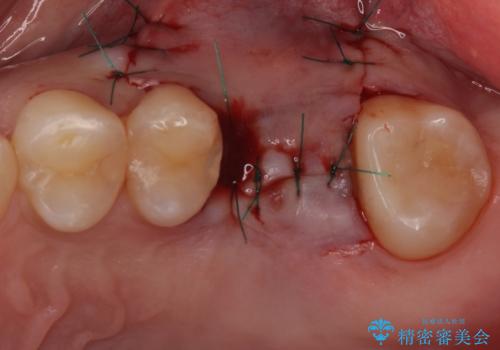

- 深い咬み合わせと前歯のデコボコ、奥歯の欠損を気にして来院された患者様です。

歯列矯正はインビザラインを使用し、矯正治療中の適切な時期に奥歯の欠損部位にインプラントを埋入することとしました。

矯正治療とインプラント治療を同じ歯科医師が担当することで、通常見られるような複数医院を行き来する煩雑さや、複数担当医の見解の違いによる治療の遅滞といった煩わしさは一切なく、スムーズに治療を進めることができました。

安定して咬めるようになり、患者様には大変満足していただきました。